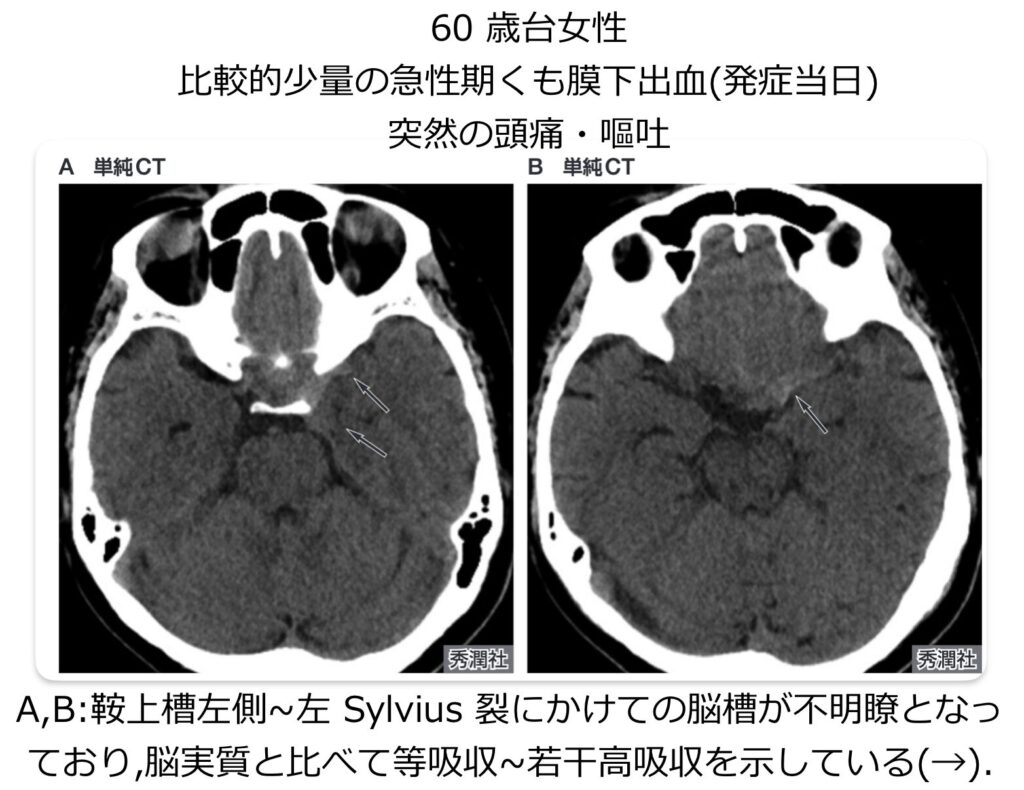

典型的なSAHの場合、頭部単純CTにおいて、脳の底部にある「鞍上槽」を中心として、前大脳縦裂、両側のシルビウス谷・裂、橋前槽、迂回槽へと血液由来の高吸収領域が広がり、いわゆる「ペンタゴン(五角形)」の形状を示します。このような典型例であれば診断は容易です。

少量の出血や、発症から時間が経過して血液の吸収値が低下している場合は、診断が困難になり見逃しの原因となります。 見逃しを防ぐためには、単に「白く光る高吸収域を探す」だけではなく、以下の視点で読影することが重要です。

- 左右差を比較する

- 脳槽や脳溝が、正常な脳脊髄液の吸収値(黒く抜ける状態)を示しているか?

- 脳槽や脳溝が不明瞭になっている部位はないか?

MRI

- 単純CTでSAHがはっきりしない場合や、発症から日数が経過している場合には、MRI(特にFLAIR像)が有用です。通常は髄液で黒く抜ける脳溝内に、FLAIR像で高〜等信号が見られればSAHの可能性が高いです(ただし、FLAIRでくも膜下腔が高信号を呈する病変・病態があります。詳しくは、「画像診断まとめ」様の「クモ膜下出血(SAH)のMRI画像診断(特にFLAIR) をご参照ください)。